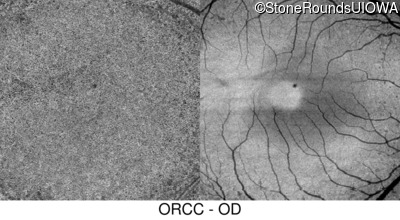

Infrared Fundus Photograph - Right - 20/50

Exemplar